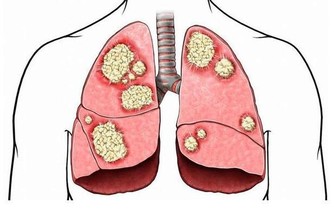

消化道出血或惡性腫瘤:消化道出血時,血液在患者的腸道中聚集。胃酸及腸道細菌將血液分解後,排出的屁有腥臭味。患腸道惡性腫瘤時,癌組織糜爛、出血,再加上細菌的分解發酵作用,也會使放出的屁有腥臭味。

腸道細菌感染:腸道內的細菌毒素通常可使腸黏膜遭到破壞,黏膜上皮細胞壞死並脫落,經過發酵之後,這些物質可產生惡臭氣體,並隨屁一起排出。